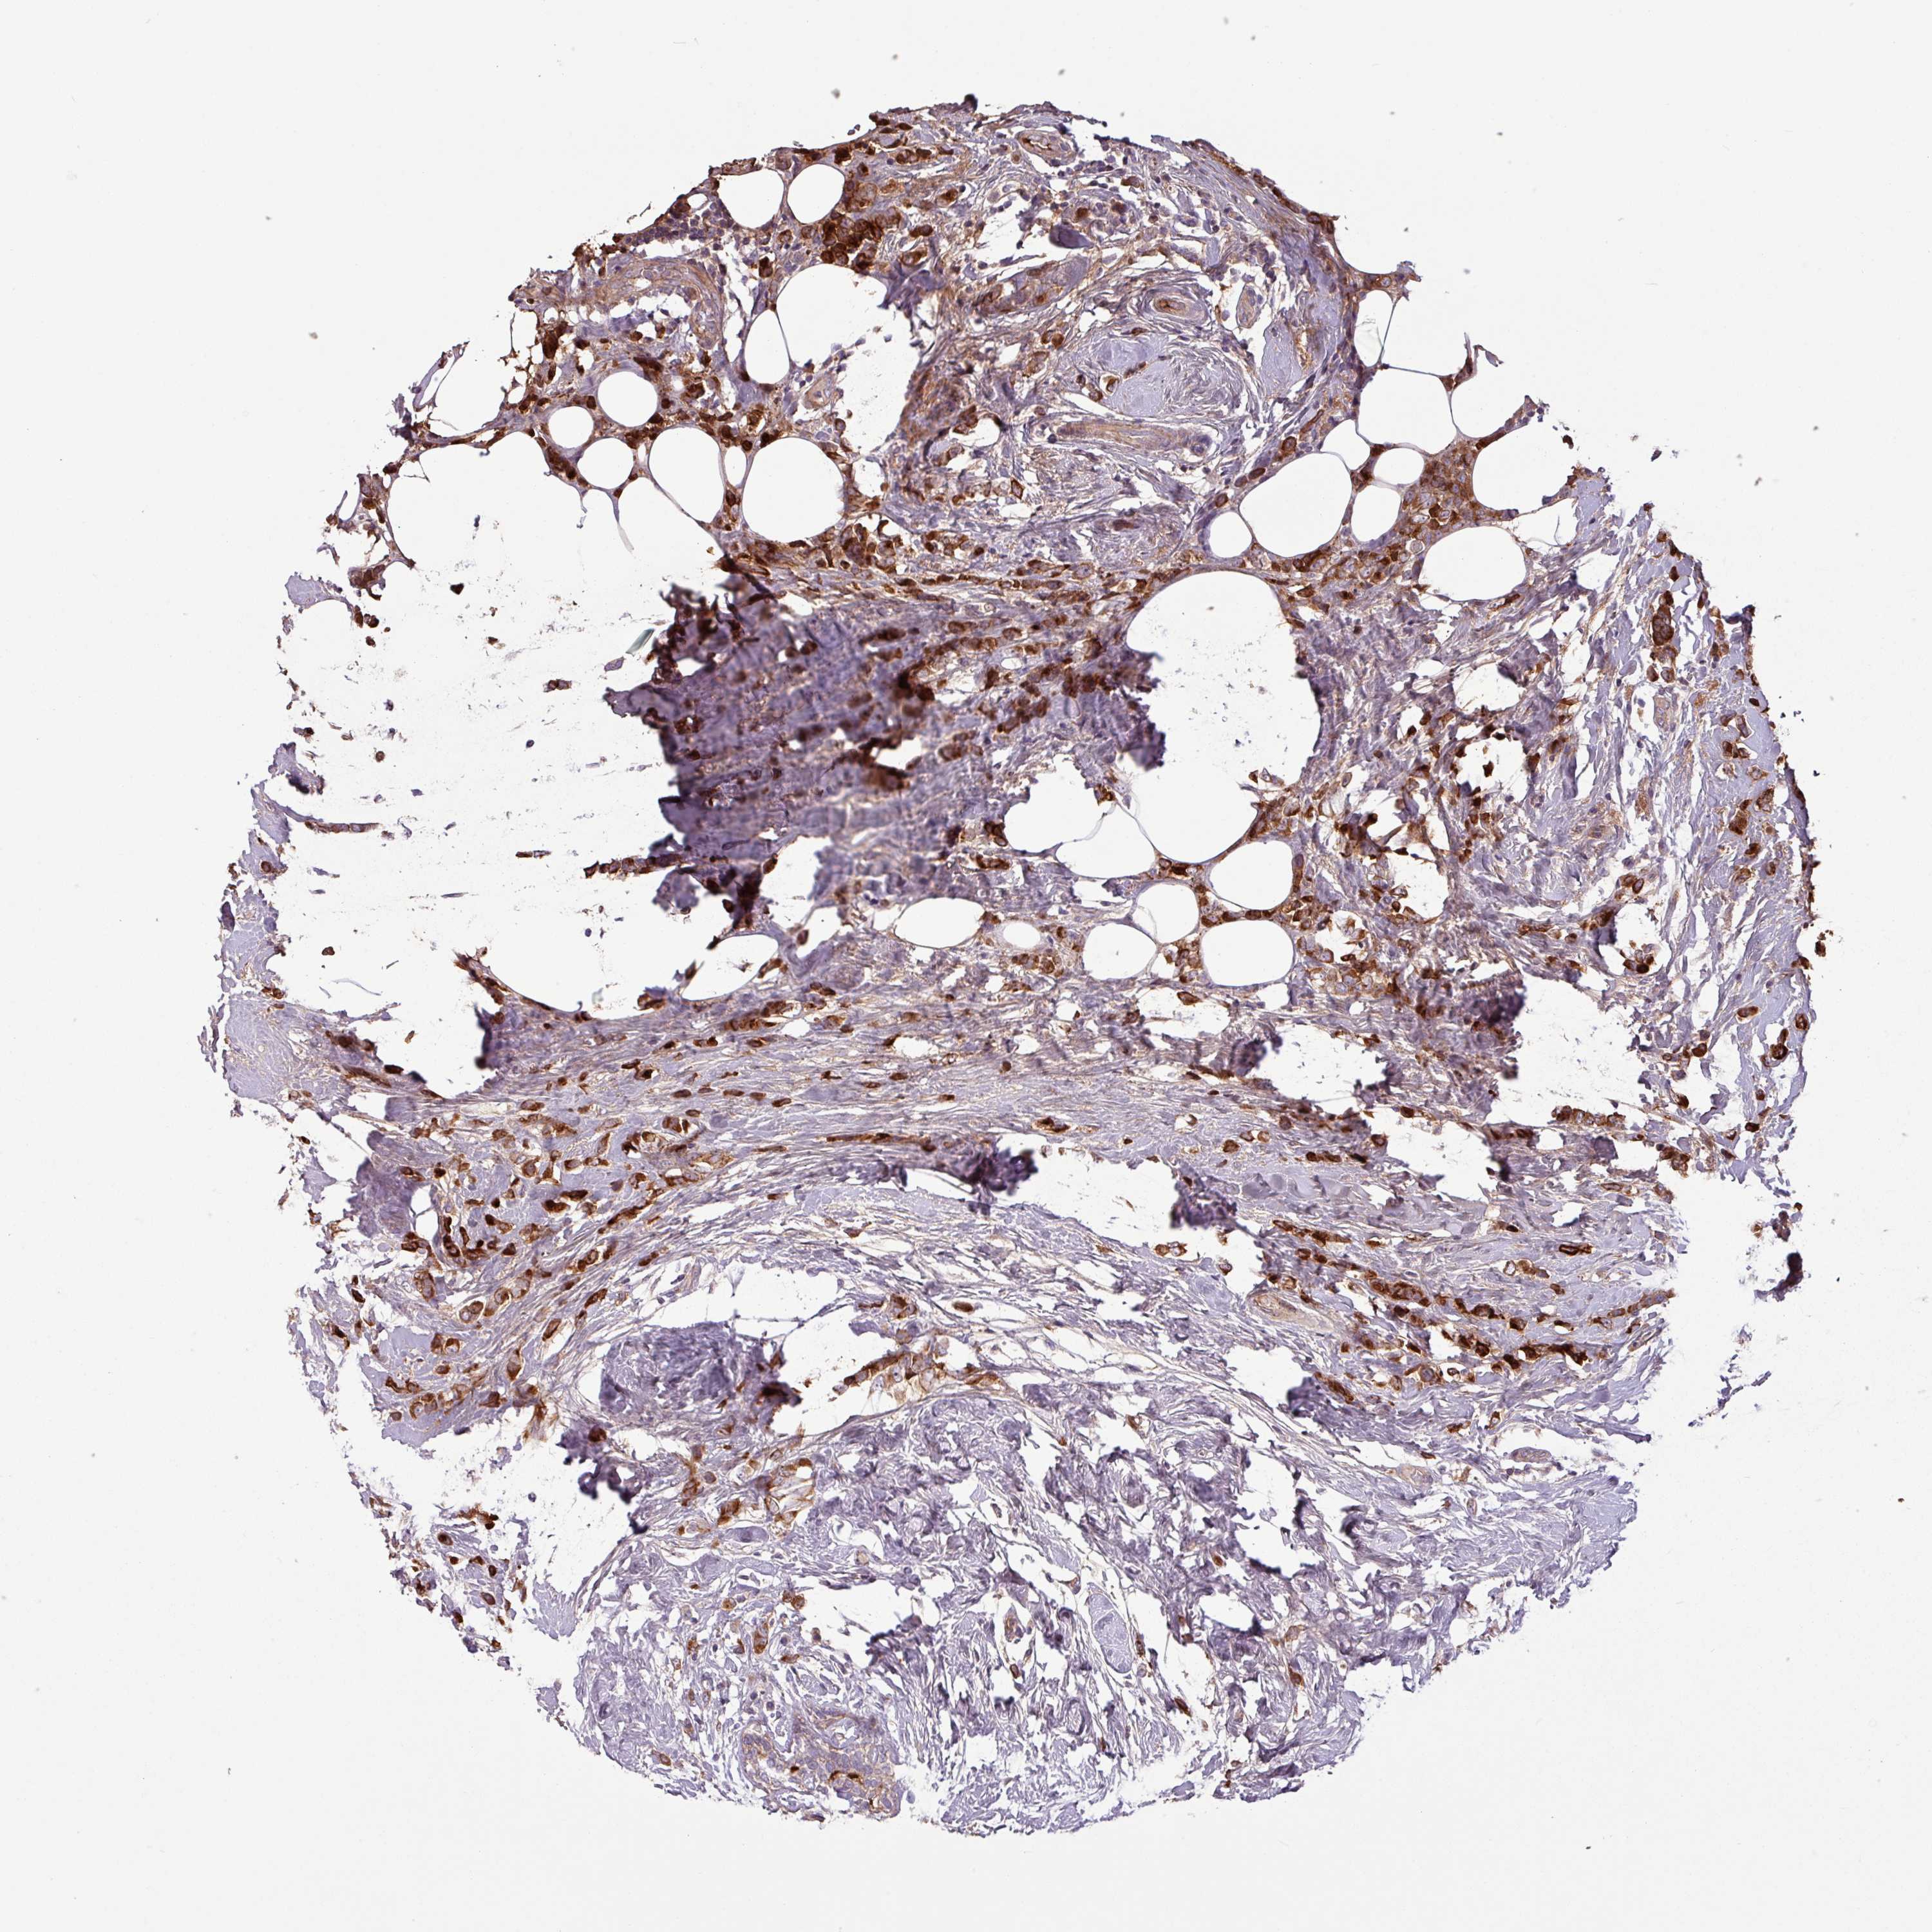

CANCER BREAST CANCER Show tissue menu

BRCA TCGA BRCA VALIDATION PROTEIN EXPRESSION